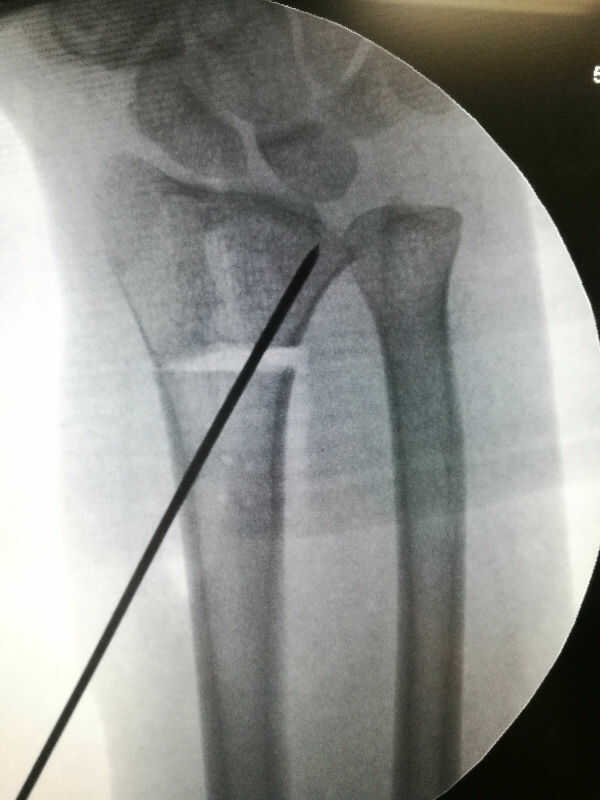

马德隆畸形手术

来自: 微社区

IMG_20190122_180809.jpg